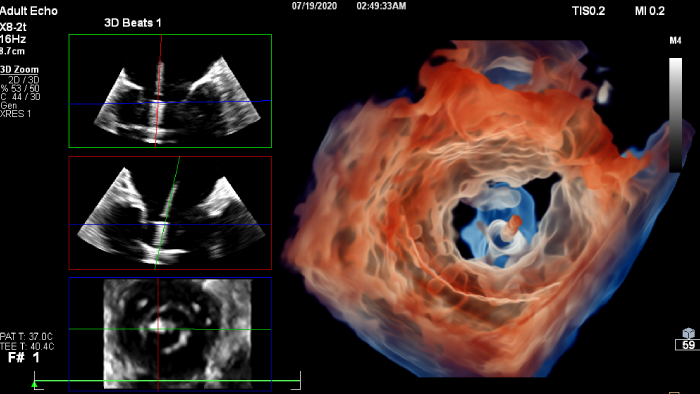

If you were registered for ESC 2023, but were not able to attend the satellite symposium, you can still view it through the ESC website. Top cardiology thought leaders addressed some of the major challenges in peri-interventional and diagnostic echocardiography, such as advancing and complementing imaging techniques during tricuspid valve interventions, a revolutionary imaging workflow for occlusion of the left atrial appendage, and the importance of first-time-right ultrasound imaging during cancer therapy.

You can still access recordings of 4 full days of hands-on workshops about best practices in multimodality cardiac imaging with expert teams. See first-time-right imaging for cardiac care, including valvular and related diseases, cardiomyopathies, and intracardiac masses and cardiac tumors.